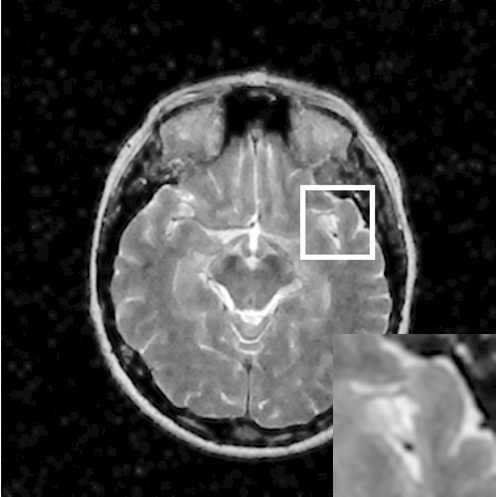

Figure 8: Reconstruction results for 25% cartesian sampling. (a) Original. (b)-(h) Reconstructed images. (i)-(n) The errors of six CSMRI methods.

As shown in Figs. 7, 8 and 9, Sparse MRI and DLMRI have a lot of unpleasant artifacts, Residual learning and U-net can eliminate most of artifacts, but are not ideal for restoring image details. However, the proposed method can reconstruct better MR images, which outperforms other competitive methods in visualization of structures reconstruction and artifacts removal. Meanwhile, we can see from the absolute error residuals for three sampling experiments that the proposed MDN algorithm restores a finer detail structure than other algorithms. Moreover, we present the PSNR and SSIM values in Table I for different algorithms, sampling masks and sampling rates. It is demonstrated that the proposed method provides better reconstruction performance and visual results than other competitive methods. We can also see the obvious improvement of all algorithms over zero-filling both in visualization. In particular, a higher SSIM value of Sparse MRI appears when using 30% variable density random sampling, however, Sparse MRI generates more artifacts than the proposed MDN.